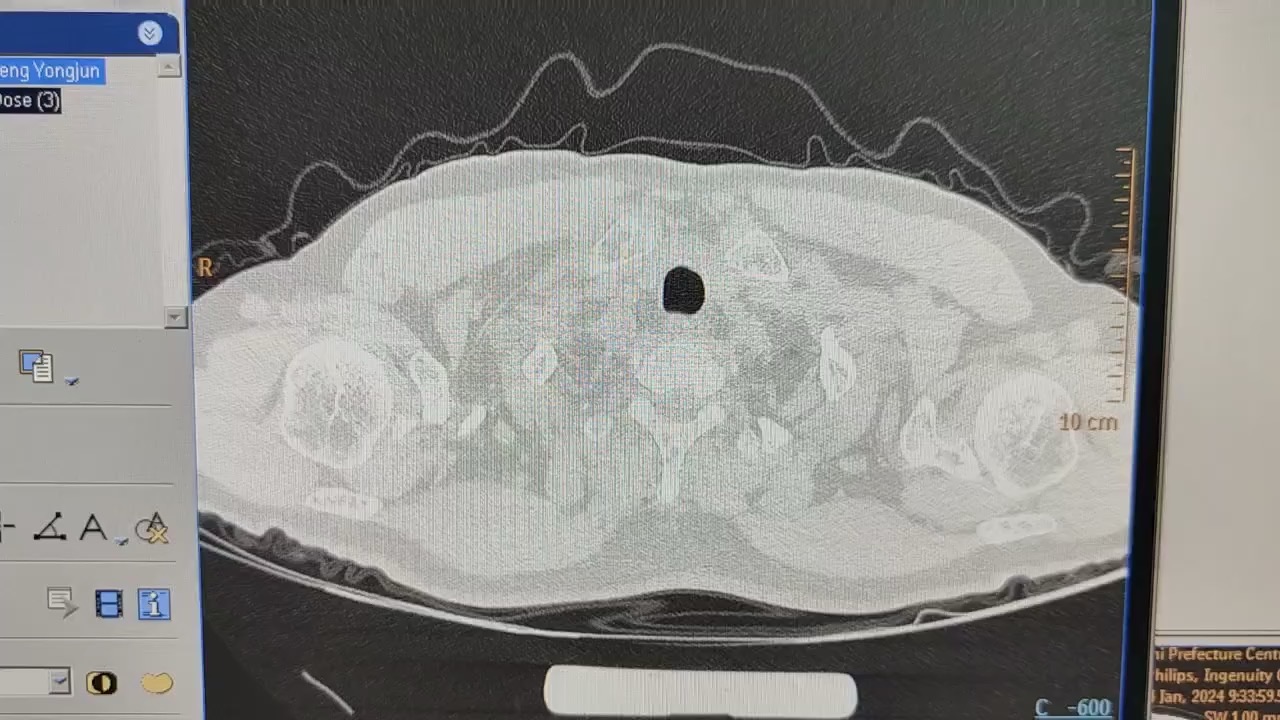

入院后查的ct,目前抗结核药依然服用